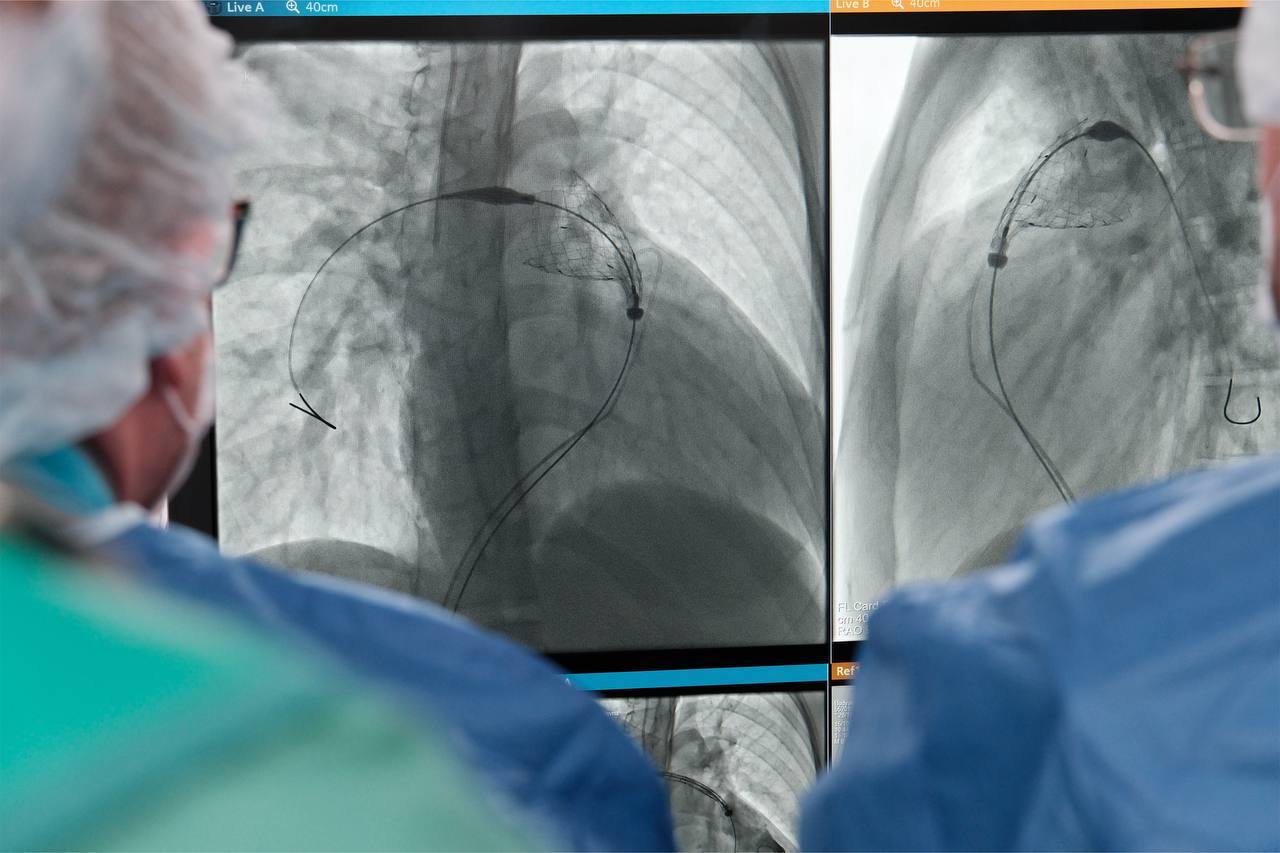

Хирурги Центра применили высокотехнологичный и малотравматичный метод по замене клапана сердца для этих пациентов – эндоваскулярную имплантацию клапанных систем.

— Мы выполнили обоим пациентам малоинвазивную операцию - эндоваскулярную имплантацию клапана легочной артерии. Данное оперативное вмешательство необходимо большинству детей, перенесших операцию на клапане в раннем возрасте. Каждому из пациентов был подобран тип клапана индивидуально: юноше имплантировали баллонорасширяемый эндоваскулярный клапан, а девушке была выполнена установка саморасширяющегося клапана. Обе операции прошли успешно и были выполнены малоинвазивным методом, через небольшой прокол бедренной вены, с подбором типа имплантата в соответствии с индивидуальными анатомическими особенностями каждого больного, — сказал Михаил Комиссаров заведующий отделением рентгенохирургических методов диагностики и лечения.